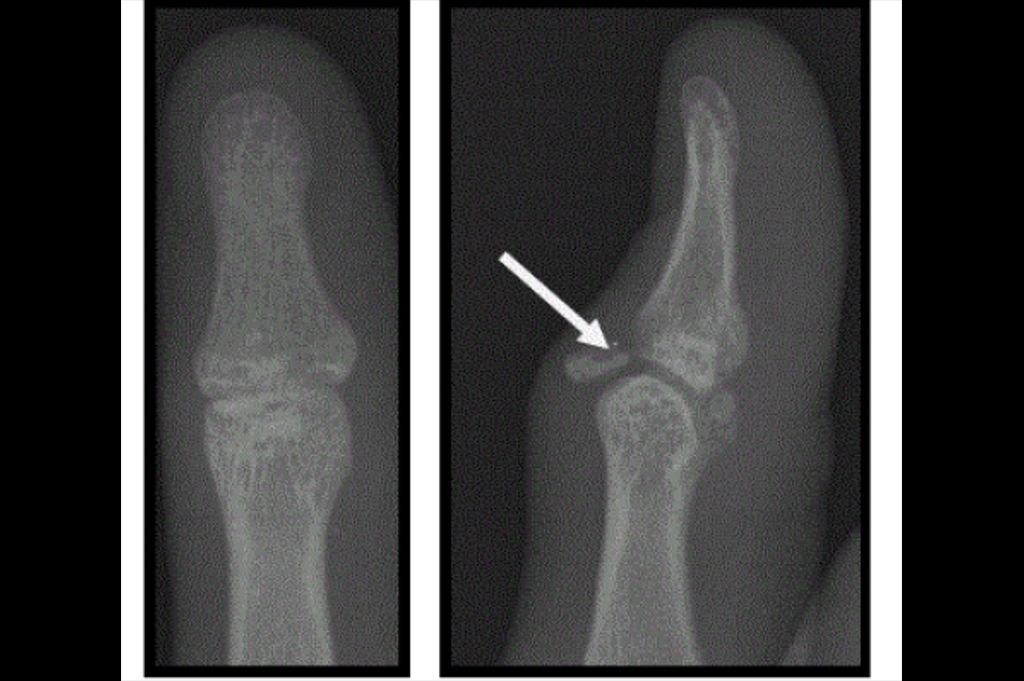

Mallet Finger